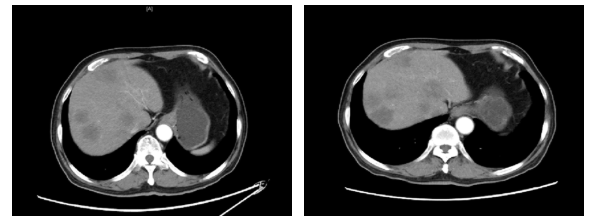

2020.4.12腹部CT:肝脏多发乏血供结节,较前明显减少并缩小(图4)。

图4. 腹部CT(左:2020.1.5,右:2020.4.12)